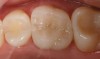

Mechanical properties are low, with flexural strength usually from 60 MPa to 70 MPa. Thus, they tend to be employed as veneer materials for metal or ceramic substructures, as well as for veneers, using either a refractory die technique or platinum foil. The microstructure of a glass is shown in Figure 1. This is an electron micrograph of an acid-etched glass surface. The holes indicate a second glass, which was removed by the acid. The veneer restoration uses a glassy porcelain (Figure 2A and Figure 2B).

The original materials had a fairly random size and distribution of leucite crystals with the average particle size of approximately several hundred microns. This random distribution and large particle size contributed to the material’s low fracture resistance and abrasive properties relative to enamel.8 Newer generations of materials have been developed with much finer leucite crystals (10 µm to 20 µm) and very even particle distribution throughout the glass. These materials are less abrasive and have much higher flexural strengths.9 In Figure 3, an electron micrograph of a typical feldspathic porcelain reveals a glass matrix surrounding leucite crystals. These materials are most commonly used as veneer porcelains for metal-ceramic restorations (Figure 4).

The most widely used version is the original pressable ceramic Empress® (Ivoclar Vivadent, www.ivoclarvivadent.com) (Figure 5 through Figure 6B).). A number of pressable materials with properties and microstructure similar to Empress are available. These include Finesse® (DENTSPLY, www.dentsply.com), Authentic® (Jensen, www.jensendental.com), PM™9 (Vita, www.vident.com), and OPC (Pentron, www.pentronceramics.com). A machinable version of Empress CAD (Ivoclar) designed for both CEREC® and E4D® CAD/CAM (D4D Technologies, www.e4dsky.com) systems for high-leucite ceramics has performed well clinically when used for posterior inlays and onlays, as well as anterior veneer and crown restorations.9-14 Paradigm™ C porcelain block (3M ESPE, www.3mespe.com) has similar properties. Machinable and pressable systems have much higher fracture resistance than powder/liquid systems and have shown excellent clinical results for posterior inlay and onlay applications and anterior veneer and crown restorations.2-7,10-14

Vitablocs are fabricated using fine-grain powders, producing a nearly pore-free ceramic with fine crystals. This was the first material specifically produced for the CEREC system and has an excellent history of clinical success for inlays, onlays, and anterior and posterior crowns.36 Sirona CEREC Blocs are fabricated from the same powders. The restoration may be characterized with external stains, or porcelain may also be added to produce a layered effect (17A and Figure 17B). These blocks are available as monochromatic, polychromatic with stacked shades as in a layer cake, and in a form replicating the hand-fabricated crowns in which an enamel porcelain is layered on top of dentin porcelain.